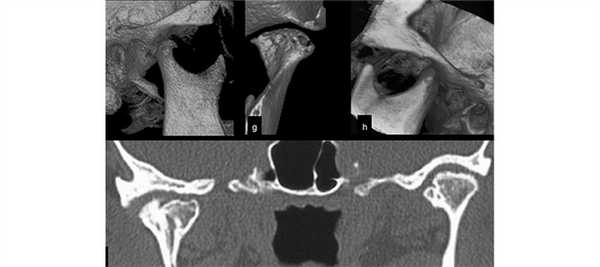

(Слева) На КЛКТ (объемный рендеринг) у девушки 19 лет с гипоплазией левого мыщелка определяется недоразвитие боковых отделов нижней челюсти слева. Угол нижней челюсти и окклюзионная плоскость слева приподняты. Костная срединная линия нижней челюсти смещена влево.

(Справа) На КЛКТ (объемный рендеринг, вид сбоку) у этой же пациентки определяется элевация угла нижней челюсти слева. Левая антегониальная вырезкам относительно хорошо выражена. (Слева) На КЛКТ (панорамная реконструкция) у этой же пациентки визуализируется правая половина нижней челюсти, имеющая нормальный размер и обычную форму.

(Справа) На панорамном реформатированном изображении нижней челюсти слева у этой же пациентки определяется уменьшение высоты тела, ветви и мыщелкового отростка нижней челюсти по сравнению с противоположной стороной. (Слева) На КЛКТ (косой сагиттальный срез) у этой же пациента визуализируется левый мыщелковый отросток нормального размера и обычной формы.

(Справа) На КЛКТ (косой сагиттальный срез) у этой же пациентки визуализируется маленький (вследствие гипоплазии) мыщелок нормальной формы, расположенный в задних отделах суставной ямки. Задняя позиция мыщелка может предрасполагать к переднему смещению диска. Смещение диска во время роста тела может быть связано с гипоплазией мыщелка.